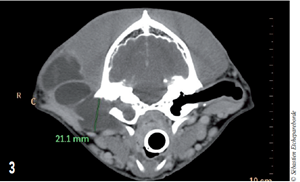

Un scanner a ensuite été réalisé. Il montre une collection liquidienne partant de la bulle tympanique droite. Cette collection est entourée d’une membrane plus dense. Une partie du kyste s’étend ventralement sous la bulle tympanique (Photo 1).

Photo 1 : Au niveau de la bulle tympanique droite (à gauche sur l’image), on note une collection liquidienne qui s’étend sous la bulle tympanique.

La collection qui fait 2 cm de diamètre à la base de l’oreille moyenne s’élargit en cône et vient envelopper le conduit auditif externe vertical (Photos 2 et 3).

Photo 2 et 3 : 2. Le kyste s’étend de la bulle tympanique et vient entourer le conduit auditif externe vertical.

3. Le diamètre du kyste depuis la bulle tympanique est de 2 cm.